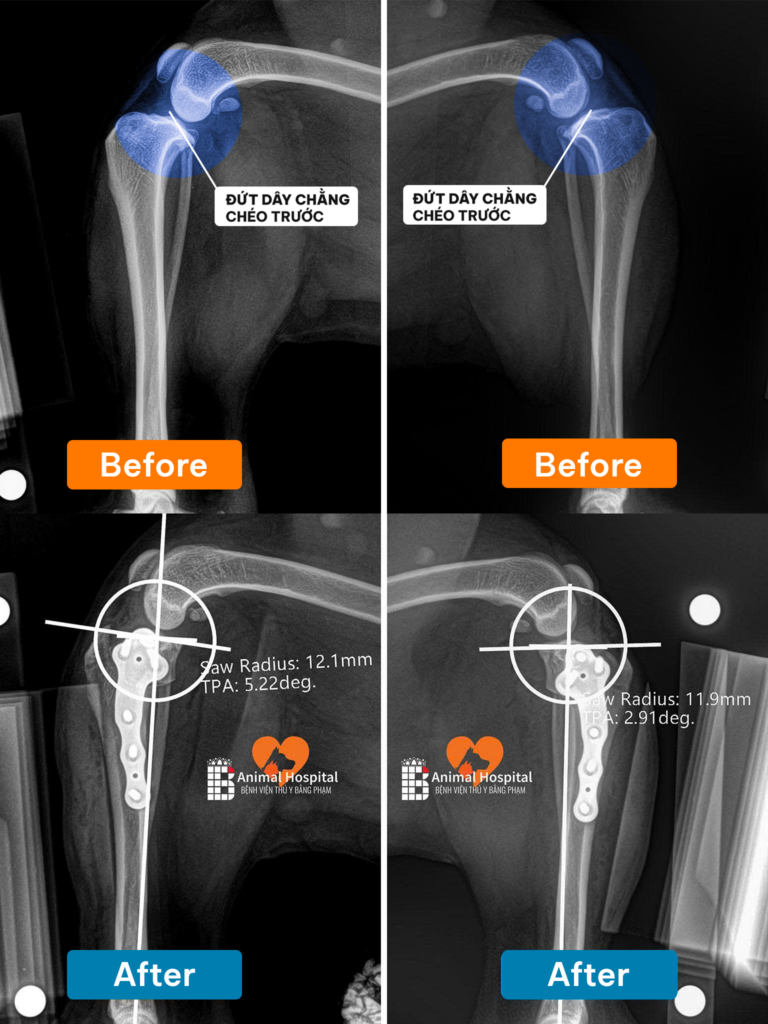

Qua thăm khám lâm sàng (Nghiệm pháp ngăn kéo trượt) và hình ảnh X-quang, bác sĩ chẩn đoán xác định: Milu bị đứt dây chằng chéo trước cả hai bên khớp gối. Khớp mất hoàn toàn sự liên kết cốt lõi, khiến mâm chày trượt tự do về phía trước, triệt tiêu động năng di chuyển và gây đau đớn dữ dội.

Với tình trạng đứt dây chằng song phương, phương pháp mổ thay dây chằng nhân tạo thông thường sẽ không mang lại hiệu quả bền vững. Giám đốc chuyên môn đã quyết định thực hiện phẫu thuật TPLO cho chó (Cắt mâm chày san bằng động lực học).

• Bác sĩ thực hiện đường cắt cong (Radial cut) trên xương chày, sau đó xoay mâm chày để thay đổi góc độ.

• Khi góc mâm chày được san phẳng, lực đẩy trượt về phía trước sẽ bị triệt tiêu hoàn toàn. Khớp gối đạt được trạng thái ổn định cơ học mà không cần đến sự tồn tại của dây chằng chéo.

• Cấu trúc xương mới được cố định ngàm chặt bằng hệ thống nẹp vít Titanium chuyên dụng thuộc tiêu chuẩn BlueSAO.